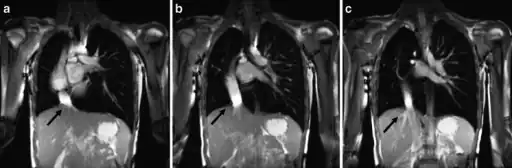

a-c) Scimitar syndrome in a young male- Breath-hold coronal 2-D steady-state free precession demonstrates the anomalous partial pulmonary venous return -

The diagnosis is made by transthoracic or transesophageal echocardiography and selective pulmonary angiography.[6] More recently by CT angiography or MR Angiography.